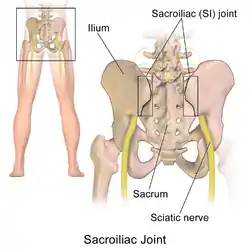

Sacroiliac joint of the male pelvis, posterior view | |

The sacroiliac joint or SI joint (SIJ) is the joint between the sacrum and the ilium bones of the pelvis, which are connected by strong ligaments. In humans, the sacrum supports the spine and is supported in turn by an ilium on each side. The joint is strong, supporting the entire weight of the upper body. It is a synovial plane joint with irregular elevations and depressions that produce interlocking of the two bones.[1] The human body has two sacroiliac joints, one on the left and one on the right, that often match each other but are highly variable from person to person.[1]

Structure

Sacroiliac joints are paired C-shaped or L-shaped joints capable of a small amount of movement[2] (2–18 degrees, which is debatable at this time) that are formed between the auricular surfaces of the sacrum and the ilium bones. However most[3] agree that there are only slight movements occur on these joints, with only 3 degrees range of motion during flexion-extension, followed by 1.5 degrees axial rotation, and 0.8 degrees lateral bending.[4] The joints are covered by two different kinds of cartilage; the sacral surface has hyaline cartilage and the iliac surface has fibrocartilage.[2] The SIJ's stability is maintained mainly through a combination of only some bony structure and very strong intrinsic and extrinsic ligaments.[5] The joint space is usually 0.5 to 4 mm.[6]

Aging changes the characteristics of the sacroiliac joint.[7] The joint's surfaces are flat or planar in early life. Once walking ability is developed, the sacroiliac joint surfaces begin to develop distinct angular orientations and lose their planar or flat topography.[2] They also develop an elevated ridge along the iliac surface and a depression along the sacral surface.[8] The ridge and corresponding depression, along with the very strong ligaments, increase the sacroiliac joints' stability and makes dislocations very rare. The fossae lumbales laterales ("dimples of Venus") correspond to the superficial topography of the sacroiliac joints.